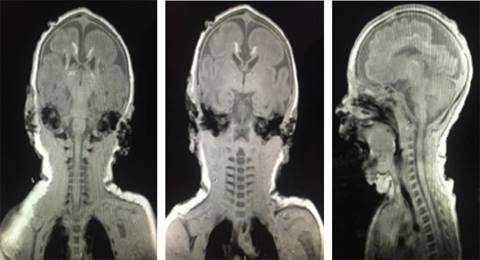

Estudios de imagen. En el USG transfontanelar se reportó: imágenes hiperecoicas compatibles con probables calcificaciones. La tomografía de cráneo: atrofia cortical y subcortical, calcificaciones parenquimatosas. Imagen de resonancia magnética: disgenesia de cuerpo calloso, paquigiria, calcificaciones subcorticales y periventriculares, disminución de volumen cortico-subcortical (Figuras 1 y 2).

Figura 2: Resonancia magnética nuclear: disgenesia de cuerpo calloso, paquigiria, calcificaciones subcorticales y periventriculares, disminución de volumen córtico-subcortical.